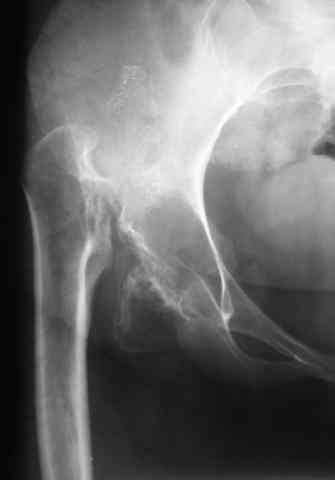

Уважаемые коллеги!В клинику обратилась больная 30 лет с жалобами на боль в области тазобедренных суставов (больше справа), ограничение движений в них.

Дисплазия была выявлена в 3-летнем возрасте, от операции родители тогда отказались. Около года назад при подъеме с кресла почувствовала резкую боль и хруст в правом бедре. С тех пор ходит только с ходунками.Выражены сгибательно-приводящие контрактуры. Справа - положительный симптом прилипшей пятки.

Мы планируем двустороннее тотальное бесцементное эндопротезирование. Первый этап - правый сустав. Чашку планируем имплантировать на свое анатомическое место, для чего резецируем часть бедренной кости. Смущают сильный остеопороз в области впадины и кривизна бедра...Ваши комментарии?-- С уважением,А. В. Вакуленко